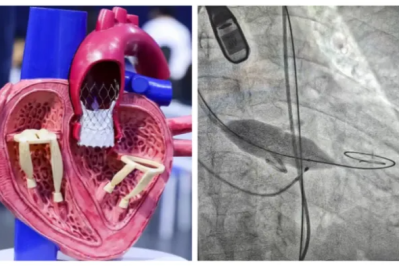

为重度主动脉瓣狭窄患者完成微创 「换心门」! 镇江瑞康医院成功开展 TAVI 术